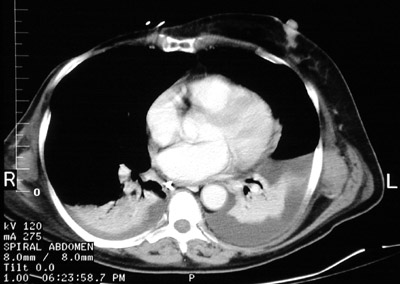

| The chest CT scan here demonstrates a large right pleural effusion. This pleural effusion resulted from right heart failure as a consequence of rheumatic mitral stenosis with chronic pulmonary congestion and subsequent hypertension. Note the enlargement of the right atrium and the right ventricle. Note also that this large effusion has produced atelectasis of the right lower lobe, characterized by a small dense crescent. In the example below, there are smaller bilateral pleural effusions, but the atelectasis is bilateral in lower lobes. |